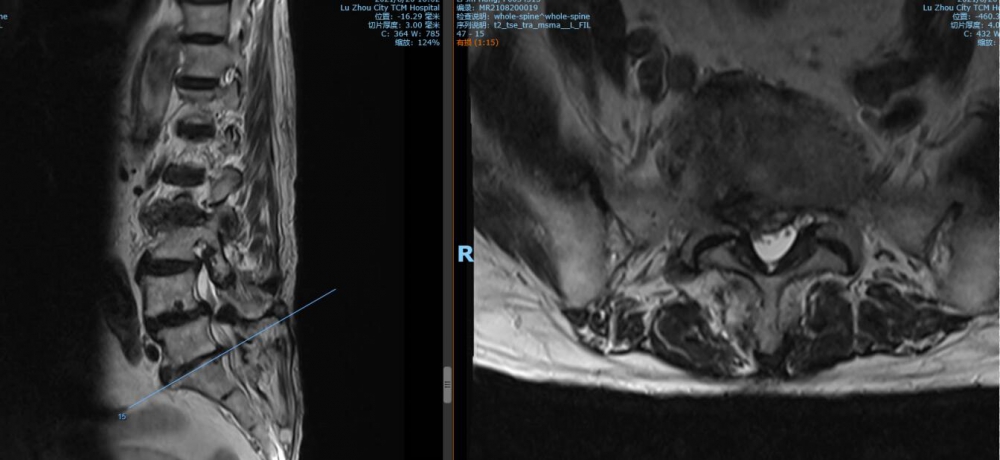

腰4 5椎間盤CT

腰4 5椎間盤MRI